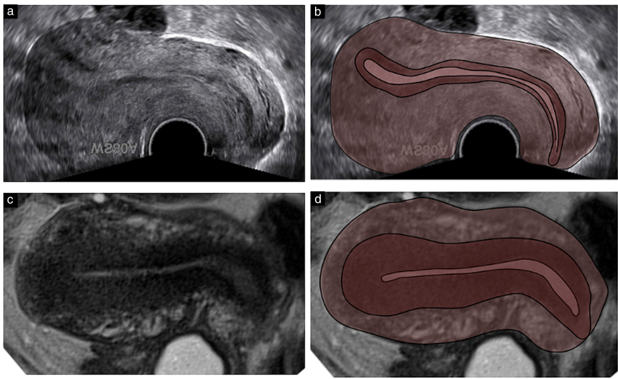

Hình ảnh siêu âm ngả âm đạo (TVS) và MRI thu được từ cùng một bệnh nhân trong cùng một pha của chu kỳ cho thấy JZ dày hơn trên MRI so với TVS, cũng như nội mạc tử cung mỏng hơn và các lớp ngoài của cơ tử cung mỏng hơn. Ở những phụ nữ khỏe mạnh, độ dày JZ đo được bằng một phần ba độ dày của cơ tử cung trên MRI, trong khi đó trên TVS chỉ bằng một phần tư. Có vẻ như một phần của lớp nội mạc tử cung được bao gồm trong phép đo JZ trên MRI hoặc một phần của JZ được nhìn thấy là nội mạc tử cung trên TVS. Theo lý thuyết này, thể tích và độ dày nội mạc tử cung lớn hơn khi được đo bằng TVS so với MRI. Sự khác biệt lớn nhất giữa các phép đo trên TVS và MRI được quan sát ở pha hoàng thể. Tuy nhiên, một nghiên cứu 3D-TVS gần đây hơn cho thấy giai đoạn chu kỳ dường như không ảnh hưởng đến chất lượng hình ảnh JZ. Nhìn chung, sự khác biệt giữa các phép đo các lớp tử cung trên MRI và TVS cho thấy rằng khái niệm JZ trong hai kỹ thuật này nào đều không hoàn toàn giống nhau. (Hình 2)

Hình 2: Hình ảnh siêu âm qua ngả âm đạo (a, b) và hình ảnh cộng hưởng từ (MRI) chuỗi xung T2 (c, d) của Adenomyosis ở mặt phẳng đứng của cùng một tử cung trong cùng một pha chu kỳ. JZ dày hơn rõ rệt trên MRI so với trên siêu âm. Trên siêu âm, JZ bị gián đoạn ở phía trước, trong khi đó, trên MRI, nội mạc tử cung và lớp cơ ngoài mỏng hơn so với trên siêu âm.